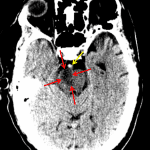

Age: 80

Sex: Male

Indication: Unresponsive

Findings

- Large area of hypoattenuation in the right hemipons extending superiorly into the ipsilateral cerebral peduncle

- Hyperattenuating appearance of the basilar artery

- Global cerebral volume loss with sequela of chronic small vessel disease

- Intracranial atherosclerosis

- Marked dilation of the frontal sinuses

Diagnosis

- Basilar artery thrombosis

Large area of hypoattenuation in the right hemipons extending superiorly into the ipsilateral cerebral peduncle concerning for acute/early subacute infarct. No evidence of substantial associated mass effect or hemorrhagic transformation.

Hyperattenuating appearance of the basilar artery, concerning for thrombosis.